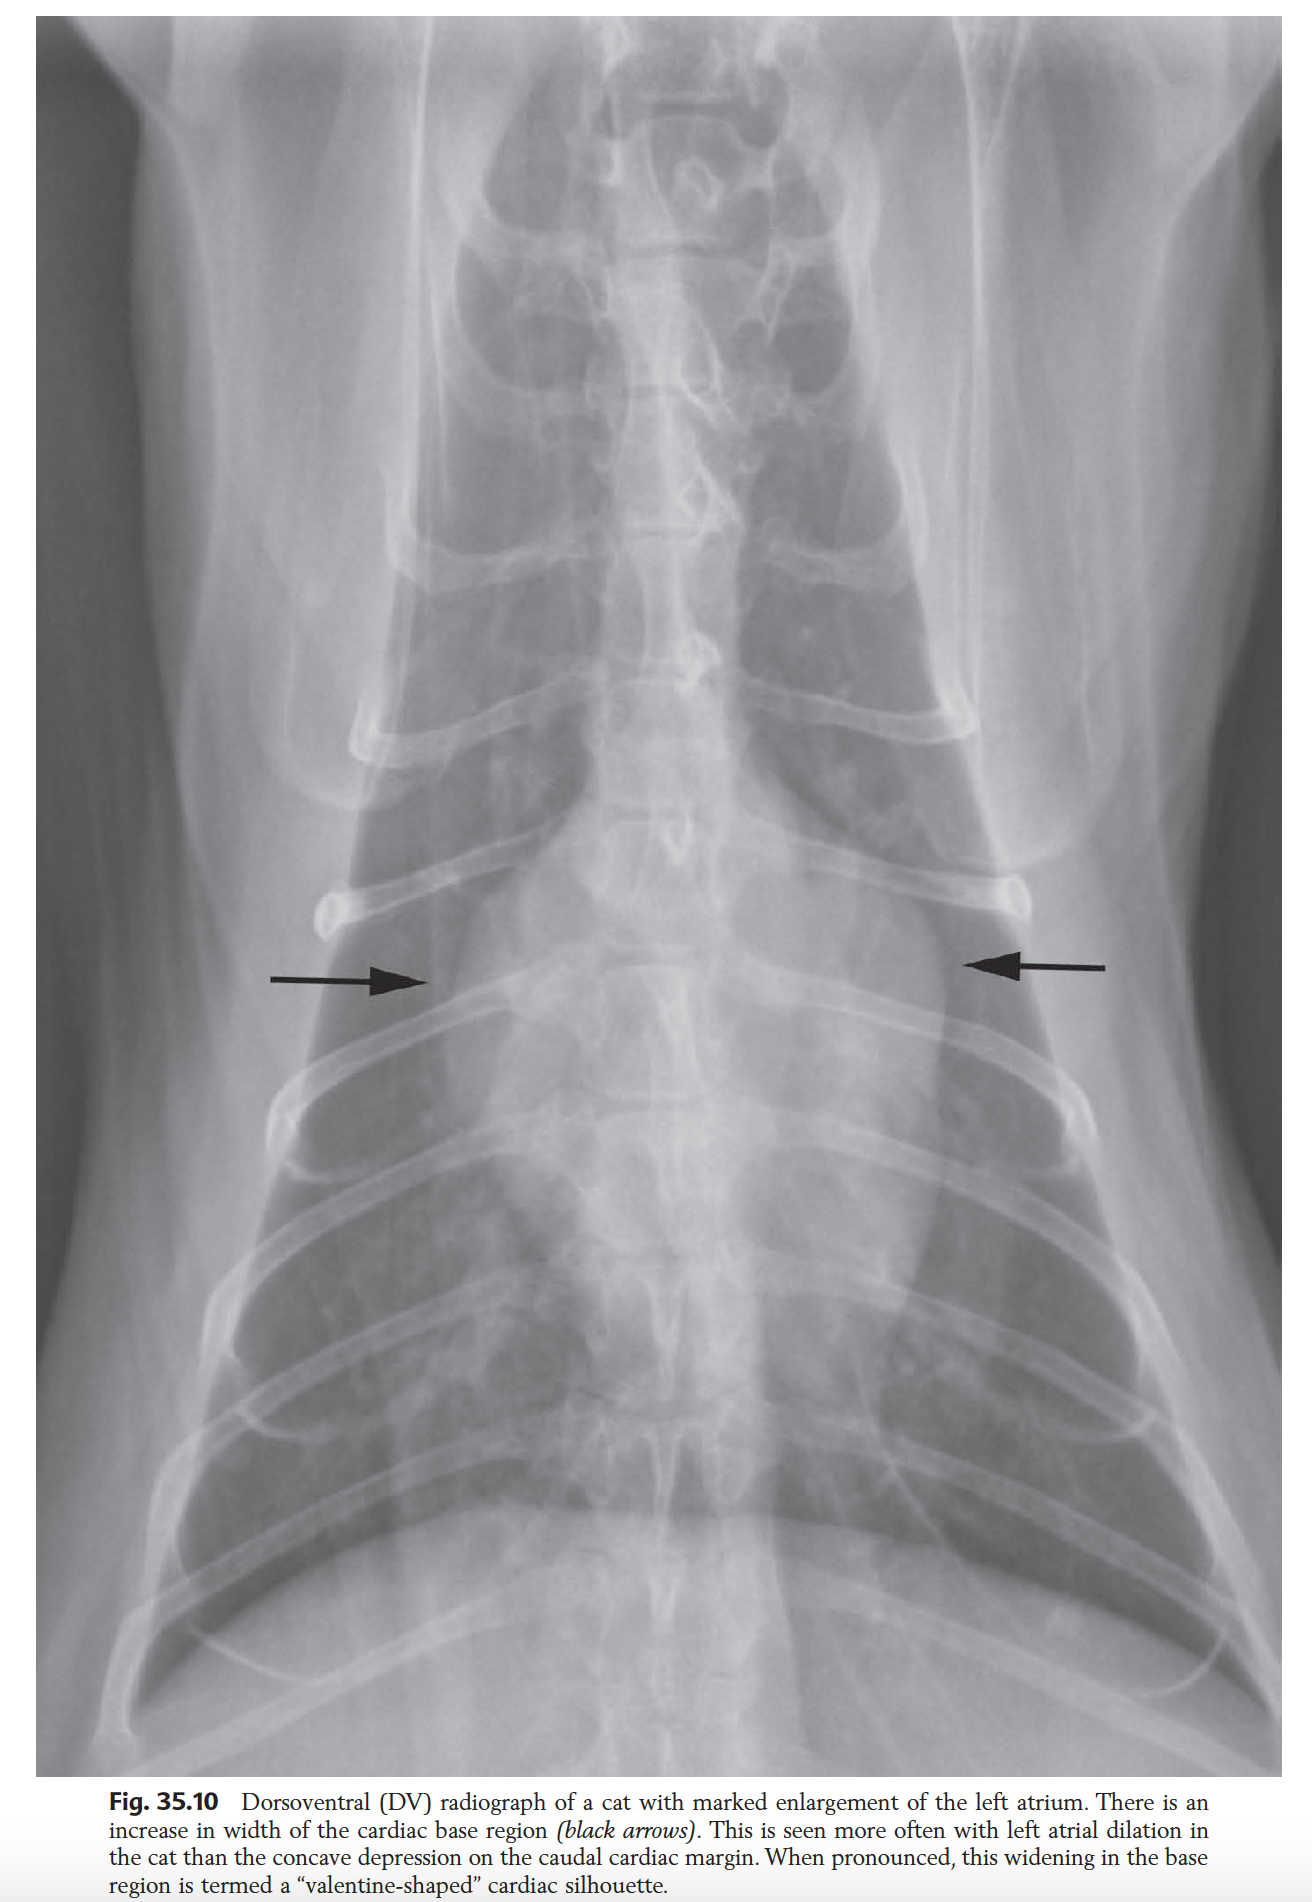

List radiographic features of LAE in the cat

**MAY APPEAR NORMAL**

Lateral:

DV:

- Valentine shape heart -> Due to increased diameter of heart base. DOES NOT REFLECT BIATRIAL DILATION!!!!